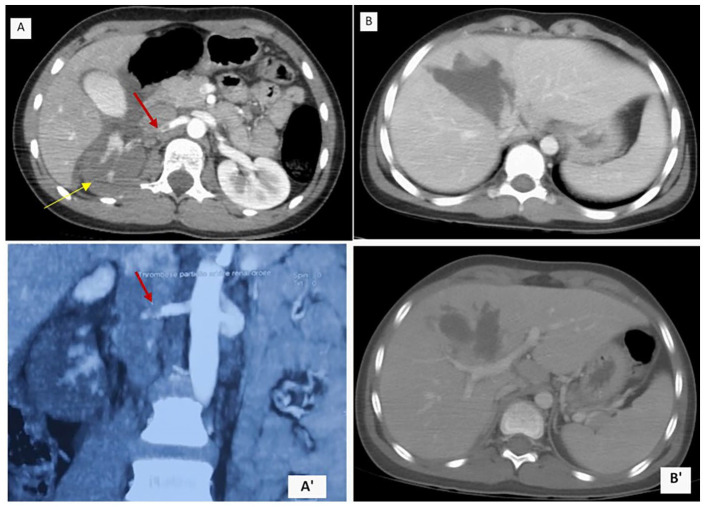

钝性外伤是儿童死亡的主要原因,而肾动脉损伤发生率不到 1%。儿童外伤性肾动脉闭塞(RAO)非常罕见,会导致同侧肾脏失去灌注。临床症状通常没有特异性,而且缺乏有关这些罕见病例在儿童中的确切发病率和治疗结果的信息。我们报告了一例单侧 RAO 病例,患者是一名 13 岁男孩,患有多发性创伤。他在一次摔倒后被诊断为右侧 RAO 和肝裂伤。尽管右肾功能丧失,但保守治疗取得了良好的效果。对于病情稳定的多发性创伤患者,及时诊断 RAO 对于优化治疗和潜在的肾脏挽救至关重要。

Blunt trauma is a major cause of death in children, with renal arterial injuries occurring in less than 1% of cases. Traumatic renal artery occlusion (RAO) in children is rare and results in the loss of ipsilateral renal perfusion. Clinical signs are often nonspecific, and there is a lack of information on the exact incidence and management outcomes of these rare cases in children. We report a case of unilateral RAO in a 13-year-old boy with polytrauma. He was diagnosed with right RAO and hepatic laceration after a fall. A conservative approach yielded favorable outcomes despite the loss of function in the right kidney. In stable polytrauma patients, prompt diagnosis of RAO is crucial for treatment optimization and potential kidney salvage.